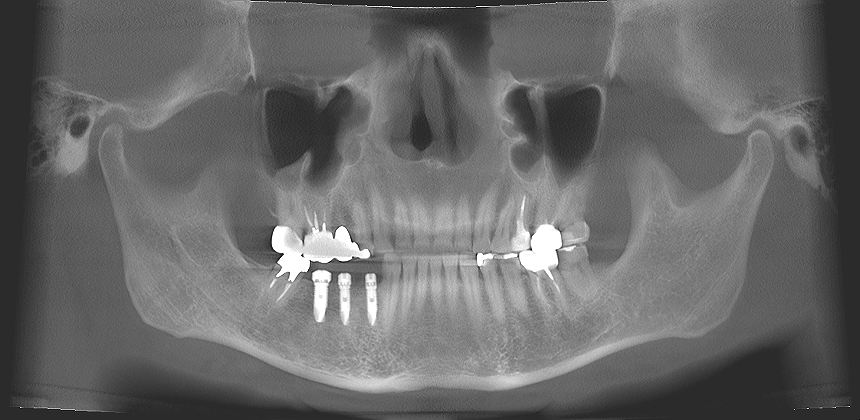

右下4,5,6番にインプラント埋入を行っていきます

インプラントを埋入しています

欠損部にはこのようにインプラントを埋入しています

埋入後になります

コーティング面がしっかりと隠れるように埋入しています

術前術後のパノラマになります